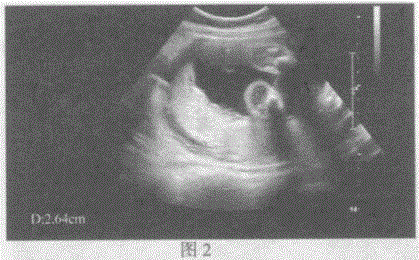

问题 图1:孕23周,宫内妊娠胎盘扫查。 图2:孕33周,宫内妊娠胎盘扫查。 按胎盘分级,图1、图2胎盘应属哪级胎盘:

选项 A.图1:胎盘0级图2:胎盘I级 B.图1:胎盘I级图2:胎盘Ⅱ级 C.图1:胎盘Ⅱ级图2:胎盘I级 D.图1:胎盘Ⅱ级图2:胎盘Ⅲ级

答案 A